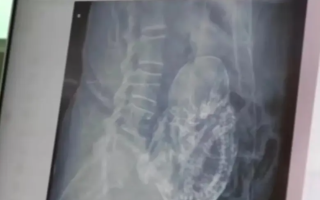

Un caso impactante en México: una mujer de 84 años de Durango descubrió que su dolor abdominal crónico era causado por un feto petrificado que había estado en su útero durante más de 40 años.

Un incidente muy extraño ocurrió en México, protagonizado por una mujer de 84 años embarazada. La mujer de Durango, México, sorprendió a los paramédicos cuando descubrieron que el dolor abdominal del que se quejaba era en realidad un feto petrificado en su útero durante más de 4 décadas. Según el diario británico Daily Star, la mujer acudió a una clínica de salud pública debido a un dolor abdominal intenso, y al examen, encontraron que estaba embarazada de un feto que no podía nacer desde hace 40 años. Los médicos creen que el feto pudo haber calcificado, en un evento extremadamente raro llamado 'feto petrificado o calcificado'. Por lo general, estas condiciones trágicas para este caso raro ocurren cuando el feto muere durante el embarazo y es demasiado grande para que el cuerpo lo absorba, por lo que se calcifica por fuera como parte de una reacción de cuerpo extraño, lo que protege el cuerpo de la madre de los tejidos fetales muertos y la protege de la infección. Los paramédicos creen que el bebé murió y se momificó en la semana 40 del embarazo después de que su crecimiento se detuvo. Los informes también añadieron que es poco probable que la madre recibiera el cuidado adecuado durante su embarazo hace unos 40 años.